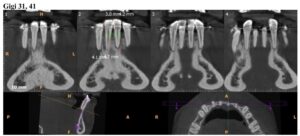

前回1月18日に歯石取りなどを終えており、歯茎の状態も特に悪化していることもなかったので、2月21日にレントゲン検査 (CBCT) 実施後、2月28日と3月28日に歯肉移植手術(下の歯左右2番と3番計4本に対し、左側と右側の2回に分けて行う)を実施することになりました。

・2026年2月21日撮影

・2025年9月13日撮影

・2022年10月1日撮影(約3年前)